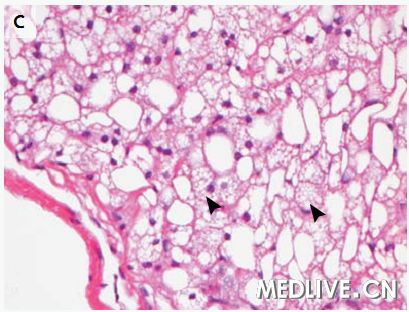

图2 肝活检标本 在低倍放大时(图A),一种小泡型的脂肪变性主要存在于(肝)中央小叶区(箭头),以及大泡型存在于门管区周围(箭)。在较高倍放大时(图B),广泛性小泡性脂肪变性存在于中心小静脉周围肝脏的中央小叶区(箭头)。被膜下区(图C)显示广泛的小泡性脂肪变性(箭头)。超微结构检查(图D)显示一个肝细胞含有不明显的线粒体和非膜结合性脂质囊泡(箭)。

米哈伊尔·利索夫斯基医师:(我们)进行了一次肝脏楔形活检。活检标本显示弥漫性重度脂肪变性(图2A、2B和2C)。小泡性(脂肪变性)形式主要见于小叶中央区,而大泡性(脂肪变性)形式存在于门管周围区域。没有肝炎、肝细胞坏死、纤维化或胆小管反应的证据,并且没有巨线粒体或可极化物质。使用淀粉酶消化的过碘酸-希夫(Schiff)染色显示肝细胞中没有胞浆内小体,并且没有糖原蓄积。铜和铁的染色以及黏多糖的胶体铁染色为阴性。电子显微镜观察证实肝细胞中存在丰富的非膜结合性脂质囊泡(图2D),并且没有显示线粒体异常、糖原沉积或其他的蓄积产物。(我们)做出了弥漫性小泡性和大泡性脂肪变性的诊断。